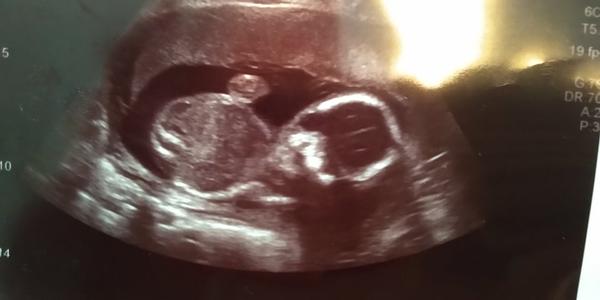

Ahoj, chtěla bych se zeptat zda se dá nějak z fotky poznat pohlaví miminka v 19tt. Doktor mi to nechce říct. :( Jsme netrpělivý s přítelem, ale víme, že jistota 100% bude až po porodu. 😀 Nevím, zda jsem de vložit foto, ale pokusím se. Děkuji.

fotka z ultrazvuku 🙂

@tehule1 já bych tedka řekla, ze je to holka. Prijde mi to jako kavovy zrno tam vlevo.